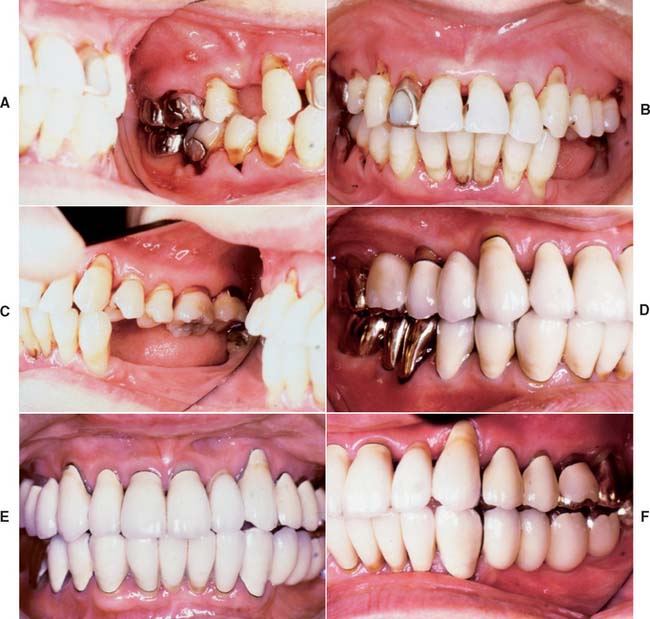

Fixed prostheses do not last forever; however, with good plaque removal, patient motivation, and average or above-average resistance to disease, a well-designed and well-fabricated restoration can provide many years of service. With poor care and neglect, even the “perfect” prosthesis or restoration can fail rapidly (Fig. 32-30). Because of exceptional host resistance, long-term success is sometimes possible with obviously defective restorations (Fig. 32-31).

Fig. 32-31 A “saddle” pontic should not be fabricated, because it makes plaque control impossible. A, However, this particular partial fixed dental prosthesis was replaced after 35 years of service. B, Despite poor pontic design, there are no significant signs of ulceration. This example illustrates the variability of tissue response as a result of differences in host resistance.

Nevertheless, at some stage, the decision about re-treatment must be made. Much depends on whether the re-treatment is part of an ongoing program of comprehensive care or whether the existing prosthesis has been subjected to years of neglect.

At the original treatment planning stage, re-treatment should be considered. This consideration may need to be general rather than specific because of difficulties in accurately predicting the pattern of future dental disease. On occasion, however, a prosthesis is designed to accommodate the eventual failure of a doubtful abutment (Fig. 32-32). With a little foresight, survey contours can already be incorporated in the retainers of an FDP to accommodate a future partial removable dental prosthesis in the event of a terminal abutment loss. Similarly, accommodations can be made for future occlusal rests by deliberately increasing occlusal reduction during tooth preparation and using metal occlusal surfaces. Furthermore, proximal boxes can be incorporated if it is anticipated that a nonrigid (dovetail) rest could simplify future re-treatment (see Fig. 32-32).

Fig. 32-32 Anticipation of future needs. A, Appearance 4 years after the restoration of an arch with periodontally compromised teeth. Three intracoronal rests (arrows) were fabricated to support a partial removable dental prosthesis (RDP). B, An additional rest (arrow) was included as a nonrigid connector for splinting the prostheses in the maxillary left quadrant. This rest is parallel to the others, and so it is available (if needed) for future support of a modified or new RDP. C, The lingual aspect of the premolar incorporates the appropriate survey contour (arrow) to accommodate such a prosthesis. D, The RDP in place. Note the third intracoronal rest (arrow). E and F, External and internal aspects of the RDP. This was cast in type IV gold, which allows the relatively easy addition of a new minor connector with conventional soldering techniques.